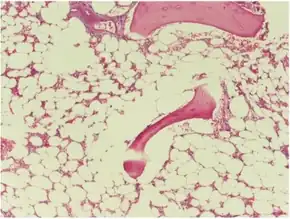

| Micrograph of bone marrow taken from a person with aplastic anemia. The bone marrow is mostly fat cells with few blood forming cells.[2] | |

The cause is unclear in 65% of cases.[3] Other cases may occur following a viral infections, due to a genetic conditions such as Fanconi anemia, or exposure to chemicals, medications or radiation.[3][4] The diagnosis may be suspected based on low blood cells together with low reticulocytes and the absence of changes concerning for blood cancer.[3] The diagnosis is confirmed by a bone marrow biopsy finding mostly fat cells instead of blood forming cells.[5]